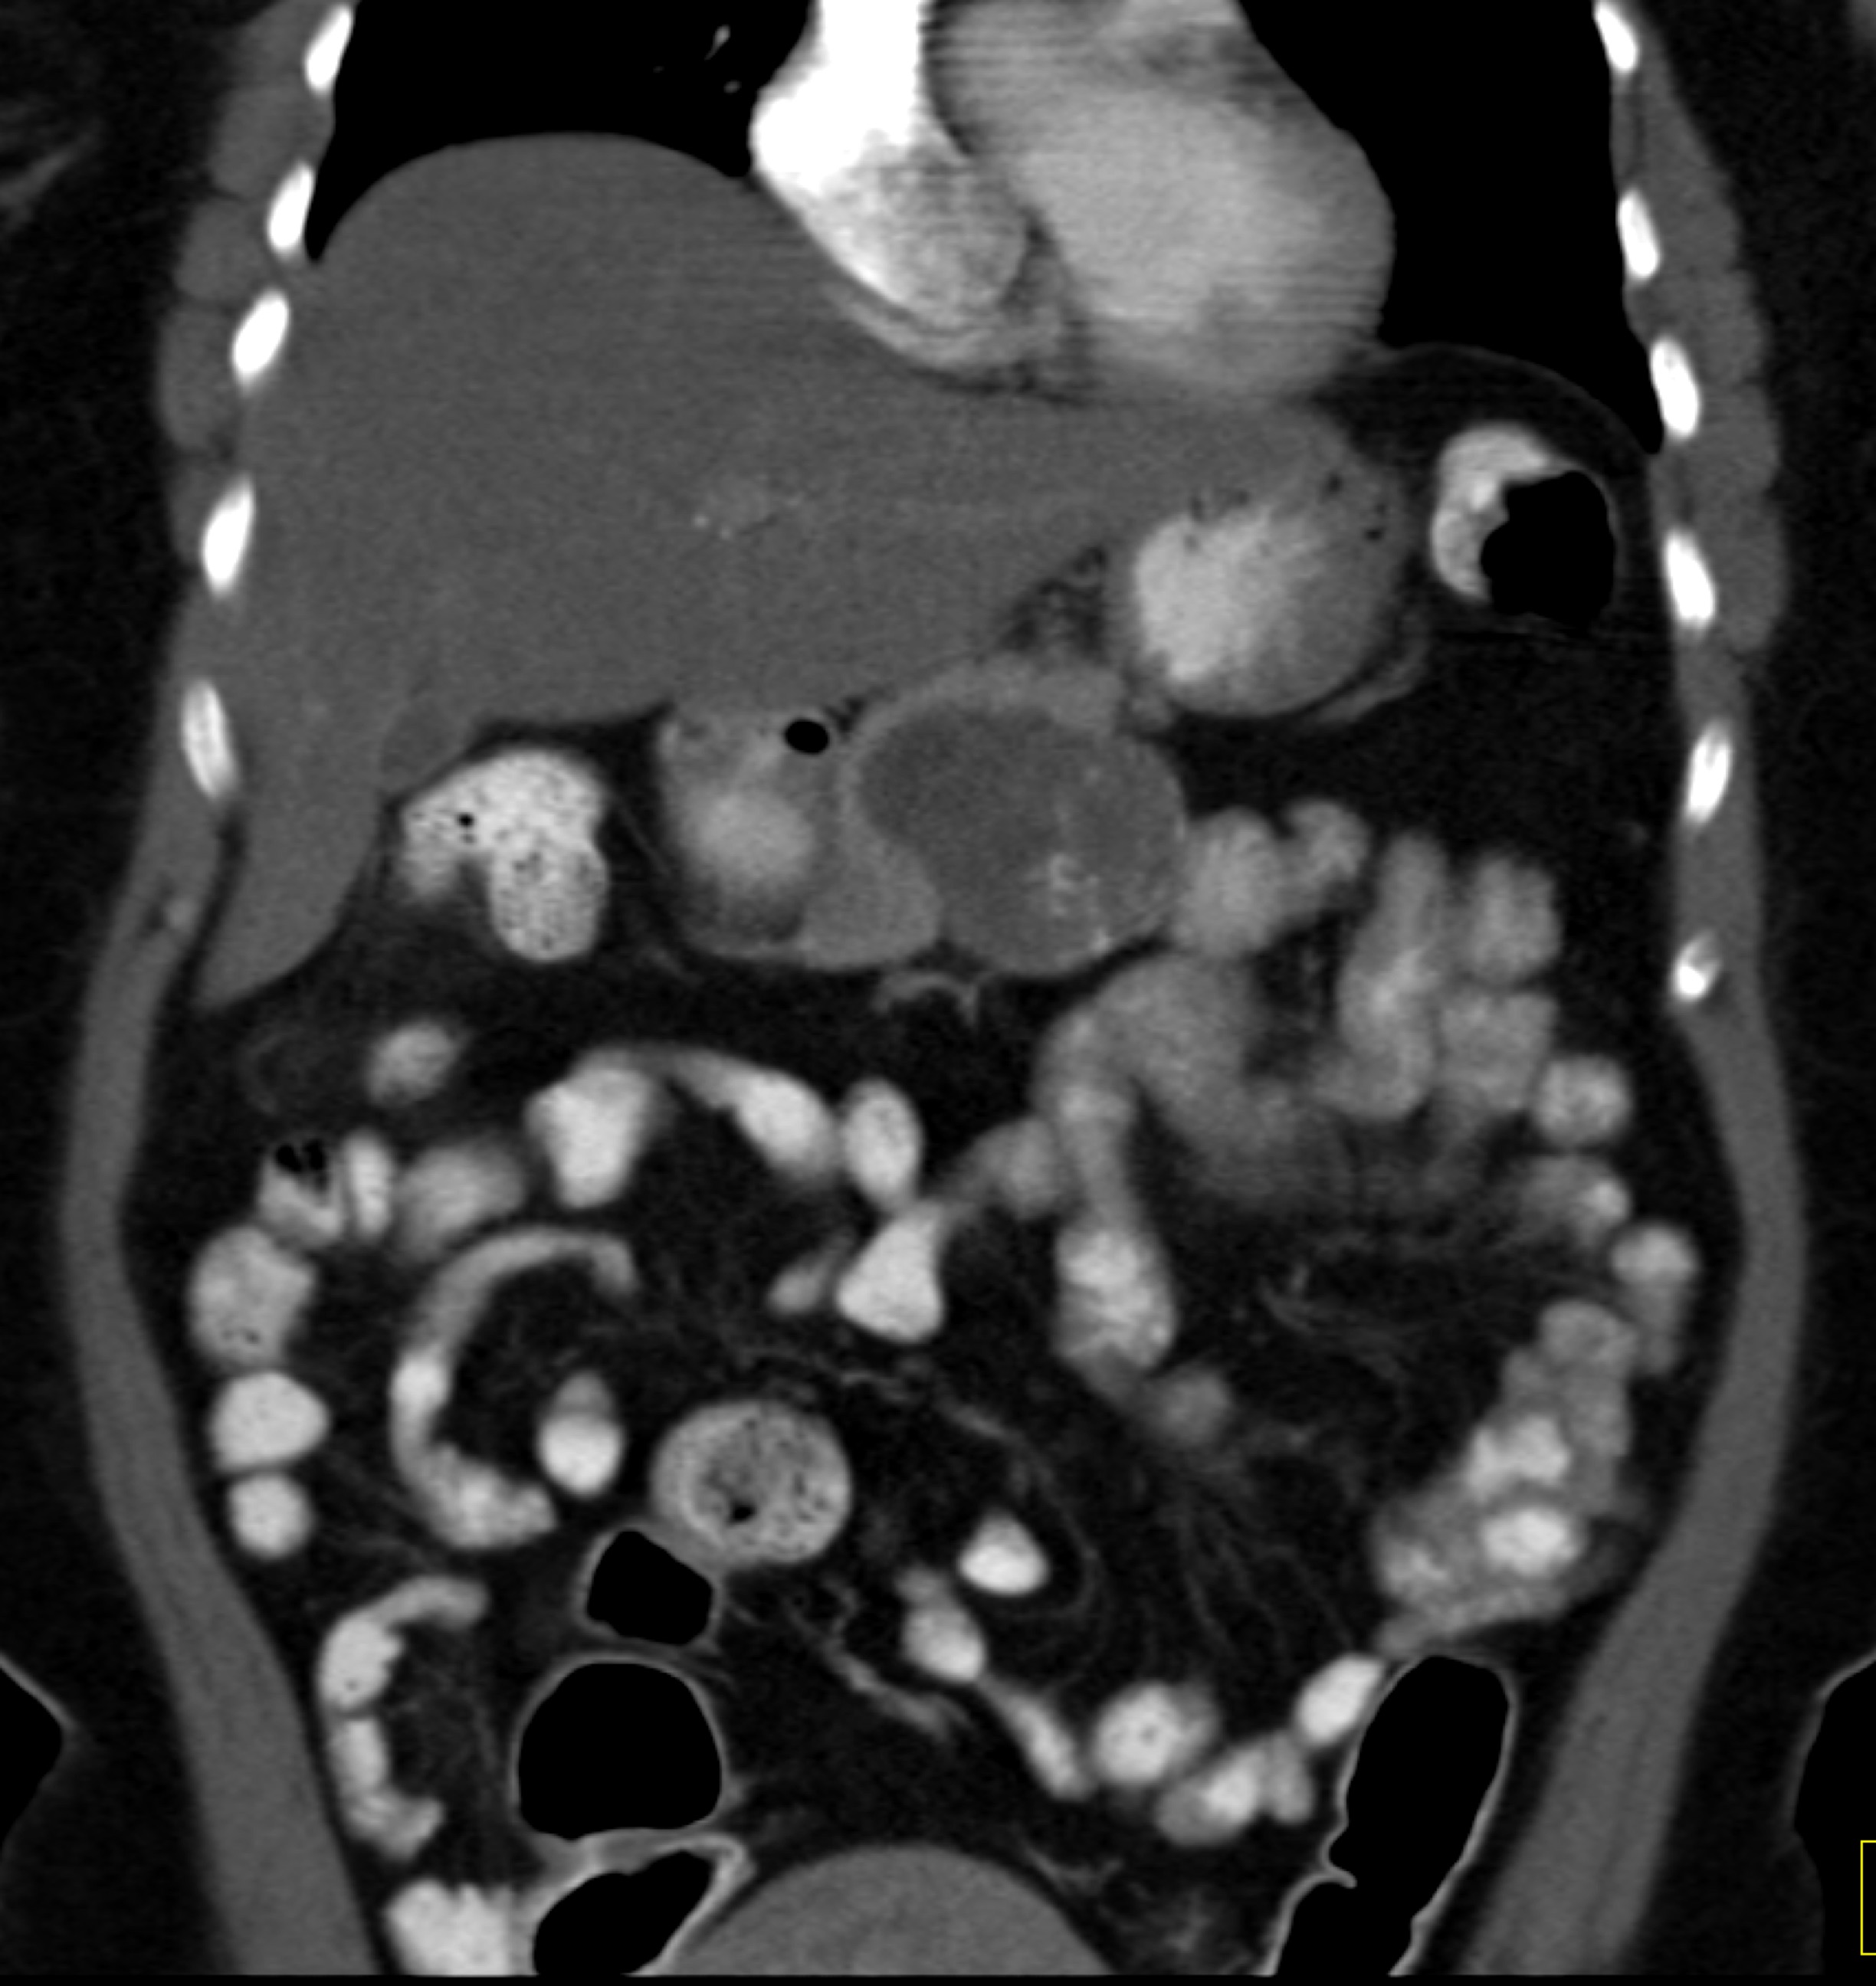

The most likely diagnosis in this 40ish year old female is

serous cystadenoma

mucinous cystic neoplasm (MCN)

IPMN

SPEN